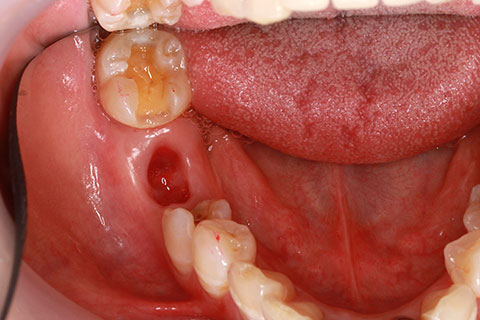

症例2

治療前

インプラント埋入時

治療後

- 年齢・性別

- 57歳男性

- 治療期間

- 3ヶ月

- 抜歯

- なし

- 治療費

- 154万円

- 備考

- 左上5.6.7 及び左下6.7欠損

- 治療内容

- 左上5.6.7と左下6.7欠損部にインプラント埋入

- 施術の副作用(リスク)

- オペによる知覚障害。インプラントによる歯肉炎。インプラント脱落。